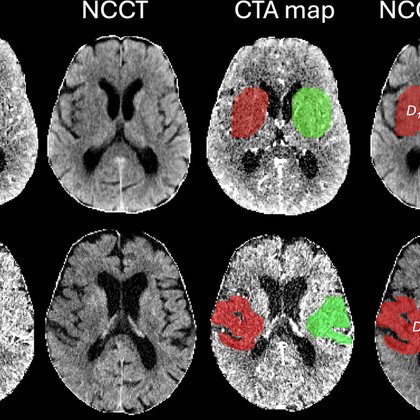

1/ 🚨 New in @Radiology_RSNA: Quantitative net water uptake (NWU) on CT predicts who benefits most from thrombectomy in large-core stroke: secondary analysis of the TENSION trial (n=207). 🧠💉 https://t.co/alLg6TE56L

#RadInTraining @RITEditor @Radiology_Editor

pubs.rsna.org

Early infarct net water uptake at admission CT modified the treatment effect of endovascular thrombectomy (EVT) on functional outcomes and may help identify patients with a large infarct core who b...